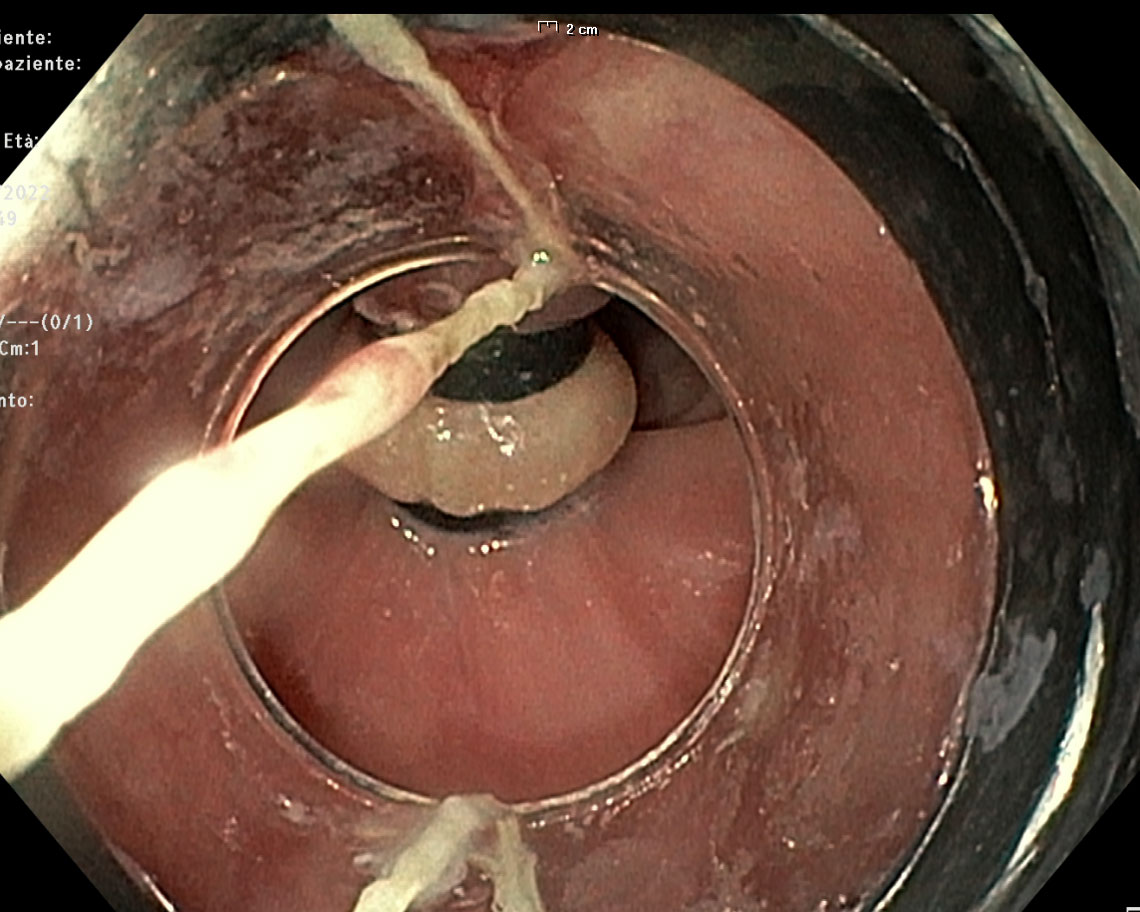

“The other side of the moon”

La Papilla di Vater vista dal Dotto di Wirsung

La foto, inviataci dai dottori Emanuele Marciano e Dario Gambaccini, è stata ottenuta mediante colangiopancreatoscopio monouso introdotto in fase intraoperatoria da moncone pancreatico